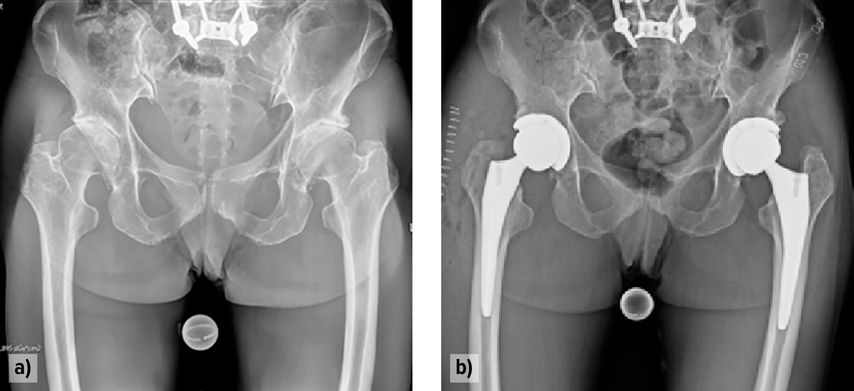

Die klinischen Vorteile der roboterassistierten Hüft-TEP zeigen sich bei definierten Risikogruppen. Insbesondere bei Patient:innen mit veränderter spinopelviner Beweglichkeit konnte – etwa bei der Hip-Spine-Klassifikation Typ 2B – eine signifikante Reduktion der Luxationsrate nachgewiesen werden.24 Auch in eigenen Fallbeispielen, etwa bei einer 47-jährigen Patientin mit fixierter dorsaler Beckenkippung, eingeschränkter Wirbelsäulenbeweglichkeit (Hip-Spine-2B) und beidseitiger fortgeschrittener Coxarthrose, konnte ohne Verwendung einer Dual-Mobility-Pfanne durch präoperative VROM-Analyse und funktionelle Implantatpositionierung eine stabile, freie postoperative Beweglichkeit erreicht werden. Auch beim 6-Monats-Follow-up zeigen sich keine Dislokationen bei freier Beweglichkeit (Abb.1+2). Ebenso profitieren Patient:innen mit komplexer Anatomie (Hüftdysplasie, posttraumatische Deformitäten) oder extrem erschwerten Bedingungen (Adipositas permagna) von der verbesserten Planbarkeit und intraoperativen Präzision.

Abb. 2: Hüfttotalendoprothesen-Implantation unter roboterassistierter Ausrichtungsoptimierung und Impingement-Analyse bei einer 47-jährigen Hochrisikopatientin mit einliegender Wirbelsäulenfusion (Hip-Spine-Klassifikation 2B) und beidseitiger Coxarthrose; (a) präoperativ, (b) postoperativ